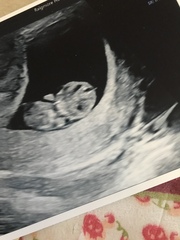

She found out a few weeks ago she was pregnant and went for a scan today.. this is what was found in her scan

They have referred her to the EPU Monday for another scan.. nothing much is being said but I wondered if you could help with any ideas as to if this is good news/ bad news or just too early? They have said there is a slight hemorrhage there also and to expect some spotting but as of yet there hasn't been any. She had a MMC in March this year also

Apparently she’s around 6 weeks but we reckon she could of ovulated later. What do you all think?

I'll attach the pics of her scan today

Thank you 🙂

@Alicejj8x it’s so difficult to say!! Obviously not a sonography expert... if your friend is likely to only be in week 5 then she more than likely wouldn’t have seen a little dot. They literally double in size from week to week at the start. Maybe that is why they have referred for another scan in a few days time to see if there is any growth? Fx everything goes smoothly for your friend xx

@Alicejj8x hopefully it's just a bit early for your friend. Being a few days out this early on makes a huge difference to what they can see. Did she wait til she had missed her period for a positive test and are her cycles regular as that could make a difference as to how far along she actually is. Did they do an internal scan or was it just abdominal?

I went for a scan at 7w and they put me back to 5+5. She had to do an internal scan to see things properly and even then she really had to take her time to see the embryos in the gestational sacs as they are just so tiny early on. My dates mean I would have had a positive test at something like 7dpo which would be v early but I suppose possible given it was a squinter & I have irregular cycles, could it be similar for your friend so she is actually just a week or so further behind than she thought & got a v early positive test?. Fx everything works out for your friend.

Yes so they are saying from her period she should be 6 weeks and they should be able to see more at 6 weeks apparently.

But her period was the 25th may so I reckon she's a few weeks behind me putting her at 4-5 weeks if not earlier possibly!

Yes they are sending her for a scan Monday so fingers crossed she'll be able to see more then

I know when I went last week they said it looked like I was 5ish weeks but we saw a heart beat so I'm thinking I'm possibly earlier on anyway

They did an internal scan but didn't say much apparently only that there was a bleed and to prepare for spotting but as of yet nothing.

I am thinking she's abit early and ovulated later I am hoping anyway for her.. ahh yes that's the same for me last week I had internal scan she said I looked 5ish weeks but didn't measure me and we saw a heart beat so I reckon I'm abit further on so I am hoping she's behind me abit and that's why they can't see anything.

Ahh ok yes that's very early isn't it I thnk the thing that worrying them is that there's no yolk sac atm just the gestational sac ..

Hopefully Monday will be able to tell her more now. Thank you xxx